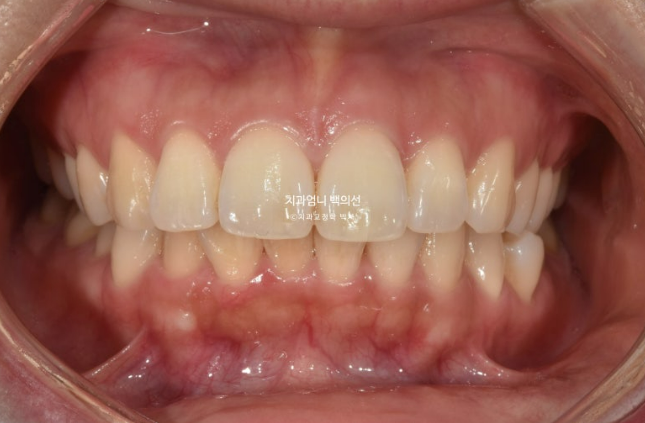

25.04

중심선은 잘 맞고

돌출입 발치교정 입술부전증 치료 후 교합도 좋습니다.

전 후 비교 보겠습니다.